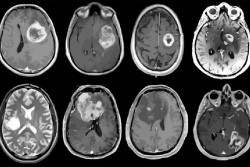

Un proceso metabólico en las células cancerosas podría conducir a un posible tratamiento para el glioblastoma

Un estudio dirigido por investigadores del Centro Oncológico Integral Jonsson de la Universidad de California Los Ángeles (UCLA), en Estados Unidos, ha descubierto que actuar sobre un proceso metabólico en personas con una mutación genética específica podría ayudar a tratar el glioblastoma, un agresivo cáncer cerebral, según publican en la revista `Cancer Cell`.